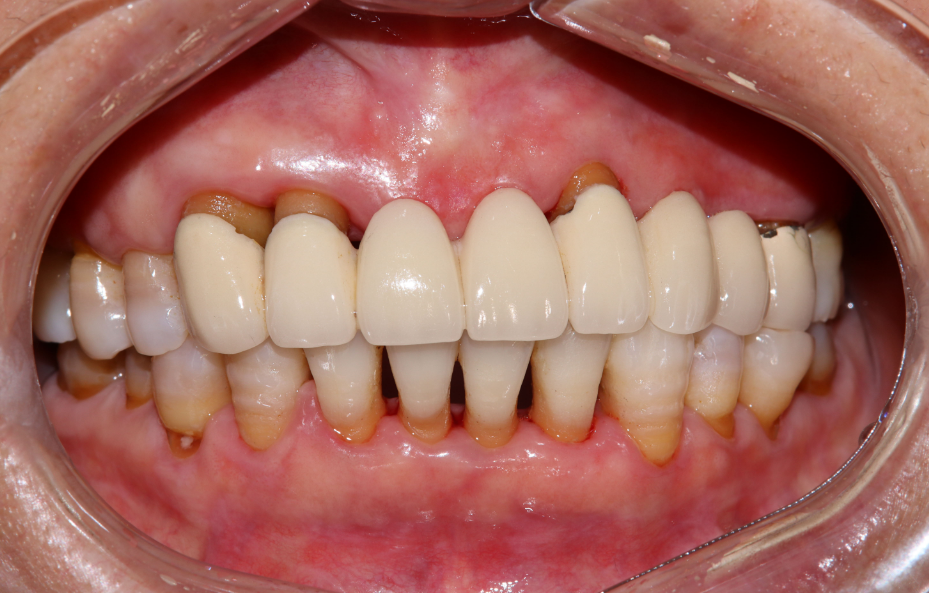

福州的兰先生今年46岁,近年来,自觉上下前牙牙缝逐渐变大,全口牙龈反复不同位置出现肿痛,咬物无力,且逐渐加重,未做牙周治疗。

我院口腔医生接诊后口内检查示:口腔卫生状况不良,局部牙龈颜色暗红,后牙区少量菌斑、软垢。龈下牙石较多(++),切牙向唇侧移位,呈扇形散开排列,出现牙间隙。影像学检查:全口牙槽骨出现不同程度吸收,尤其上排牙吸收至根中下段。

牙周内窥镜辅助下,给予牙周基础治疗2个月后,牙龈肿胀消退、色粉红、质韧,深牙周袋明显减少,探诊无再出血

治疗前